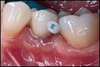

Au Cabinet : Traitement du déchaussement par un surfaçage autour de chaque dent

Au Cabinet : Tout nos détartrage sont accompagnés d’un aéro-polissage